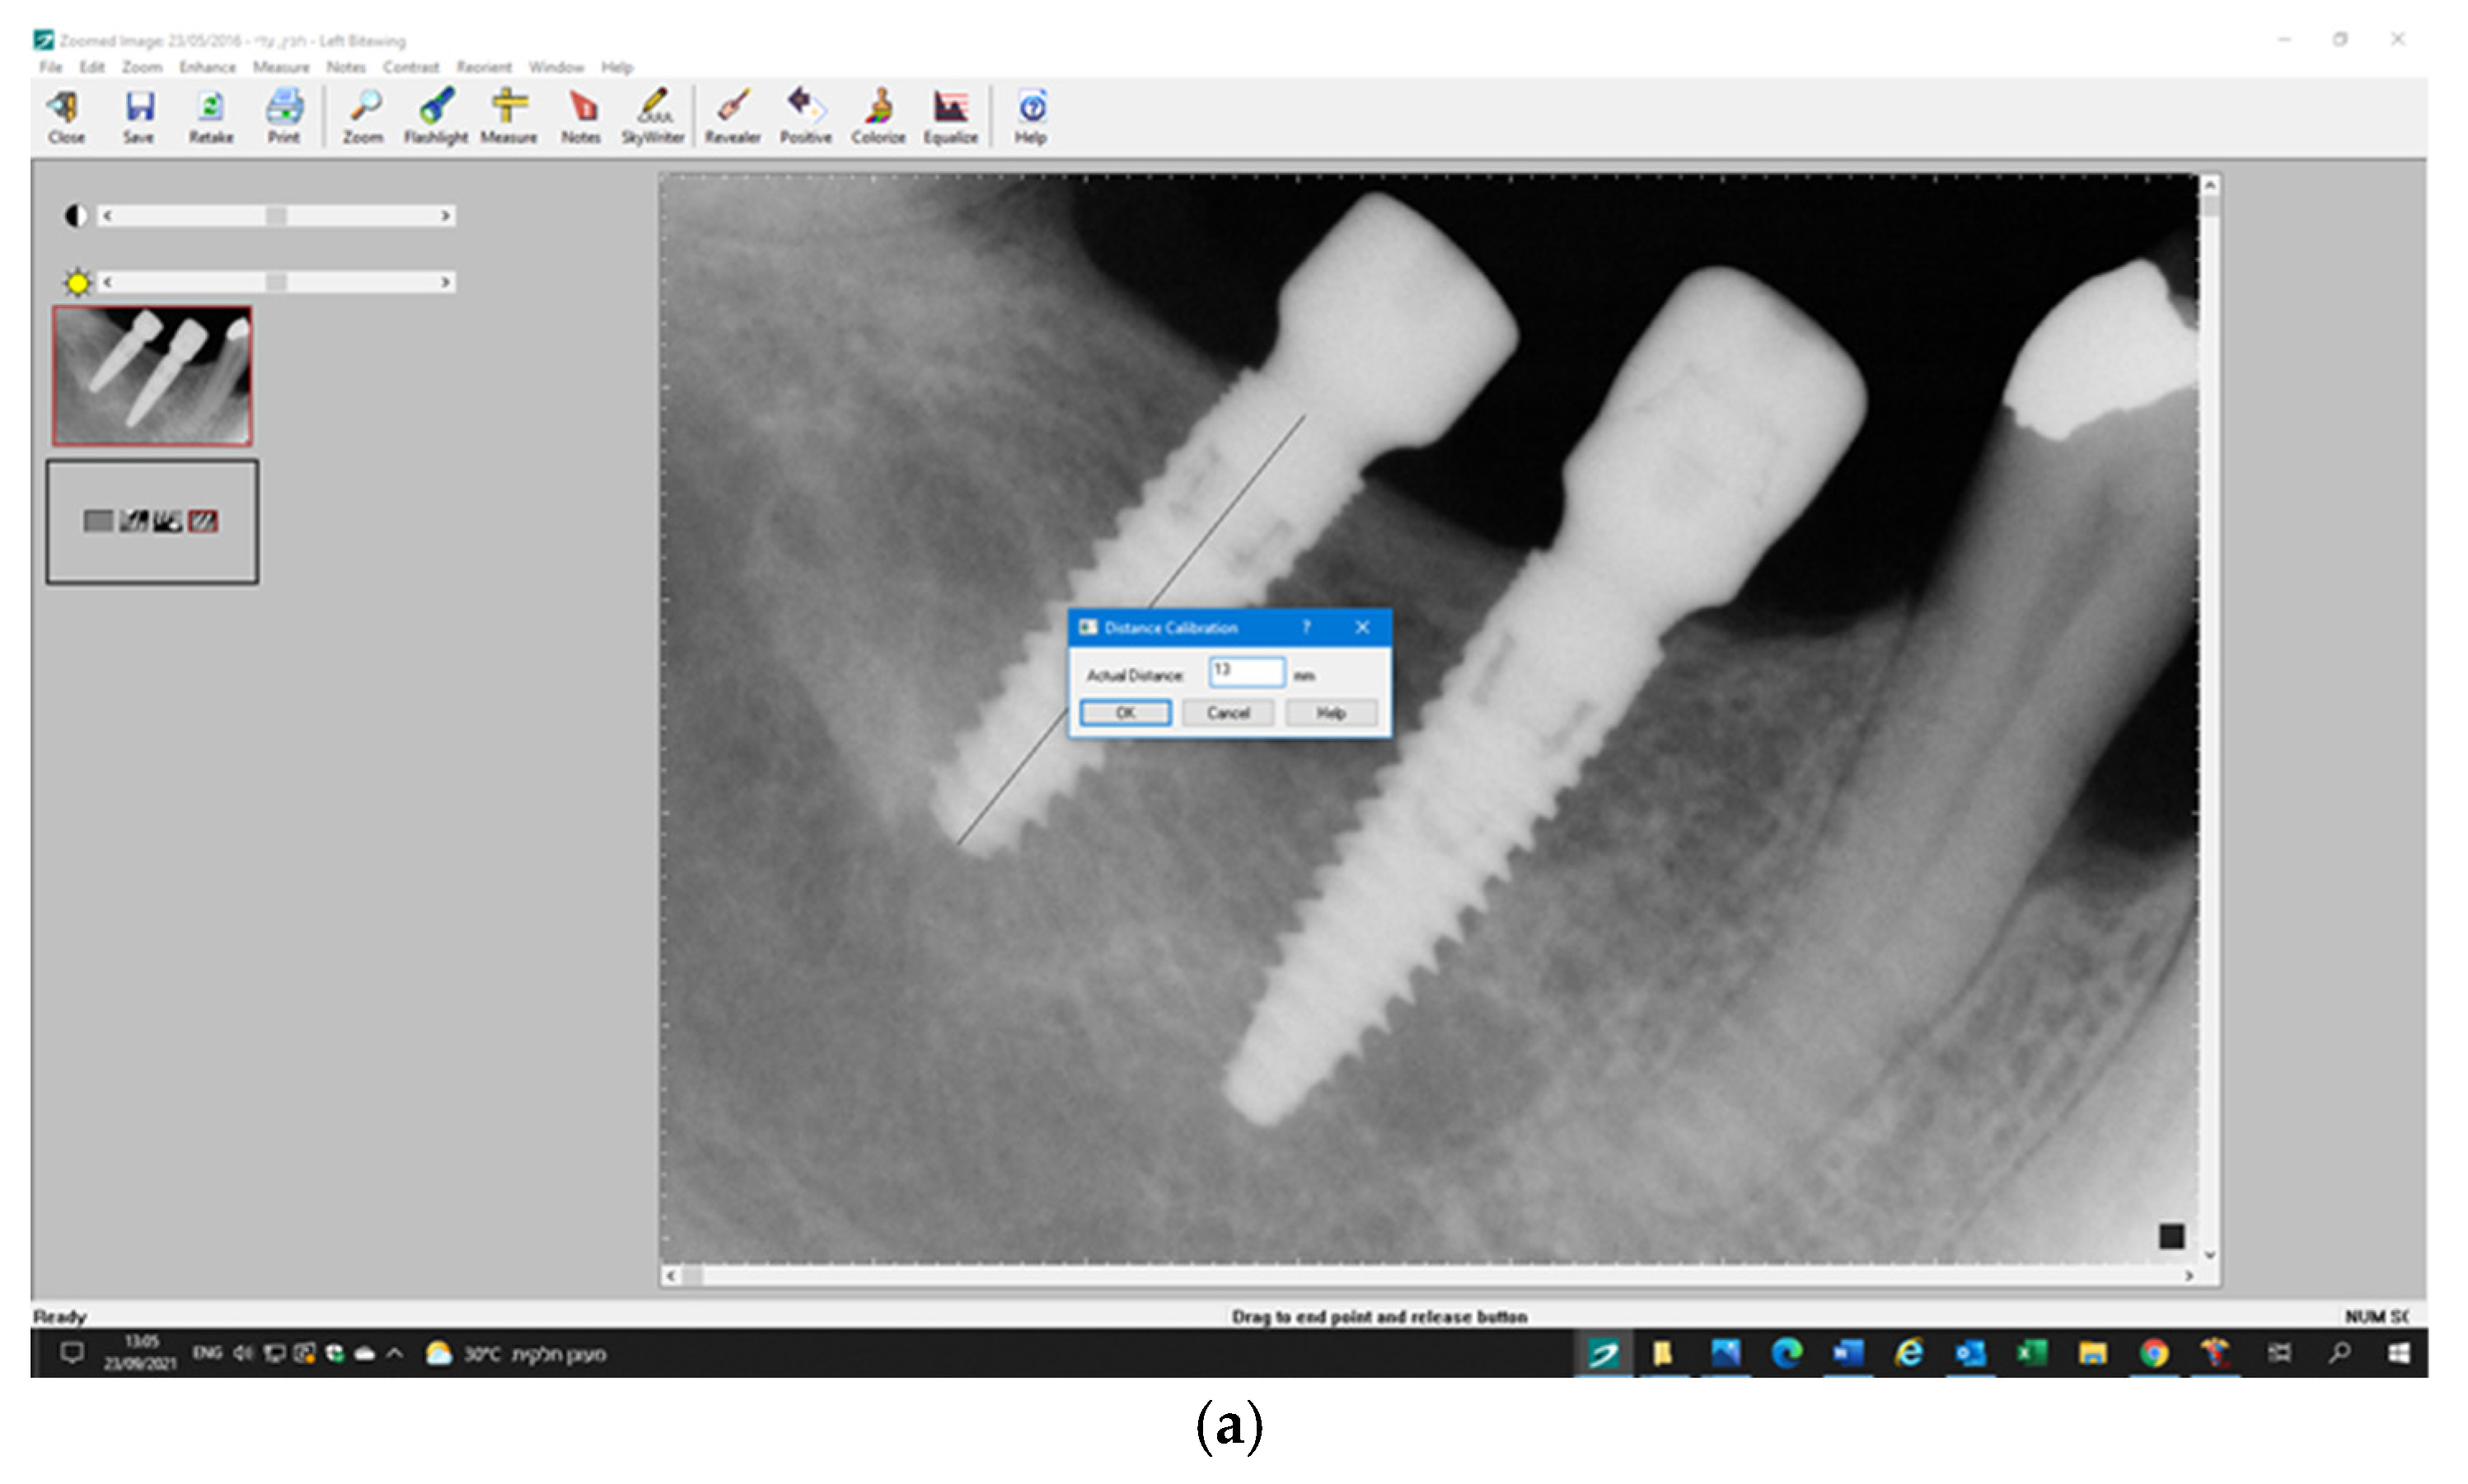

3.5. Radiographic Measurements

5.2. Marginal Bone Level